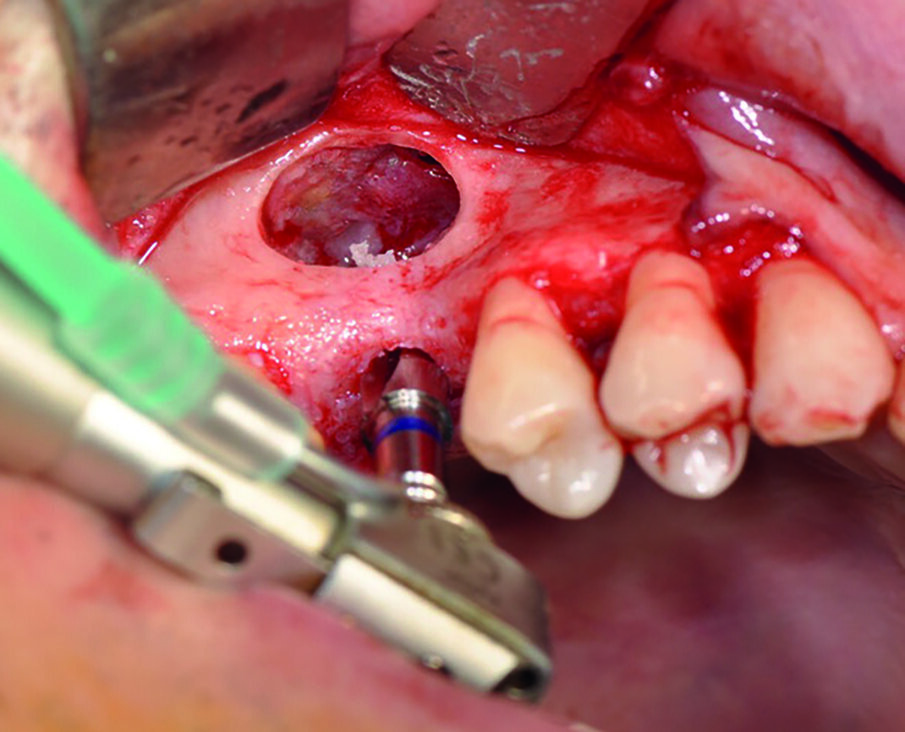

- Passaggio della fresa lanceolata (Fig. 4);

- Passaggio della fresa 2,1 (Fig. 5);

- Passaggio della fresa 2,5 (Fig. 6);

- Passaggio della fresa 3,4 (Fig. 7);

- Passaggio della fresa 3,8 (Fig. 8);

- Passaggio della fresa 4,5 (Fig. 9).

Apporre osso sul fondo della cavità prima di posizionare l’impianto permette, infatti, di non lasciare spazi vuoti nel seno mascellare che, se invece fossero presenti, potrebbero compromettere la durata del trattamento implanto protesico nel tempo. Nella fase successiva si procede all’inserimento dell’impianto way milano 4,5 per 10 (Fig. 12) che nei tre mm di osso residuo corticalizzato, trova una stabilità superiore ai 35 N (Fig. 13).